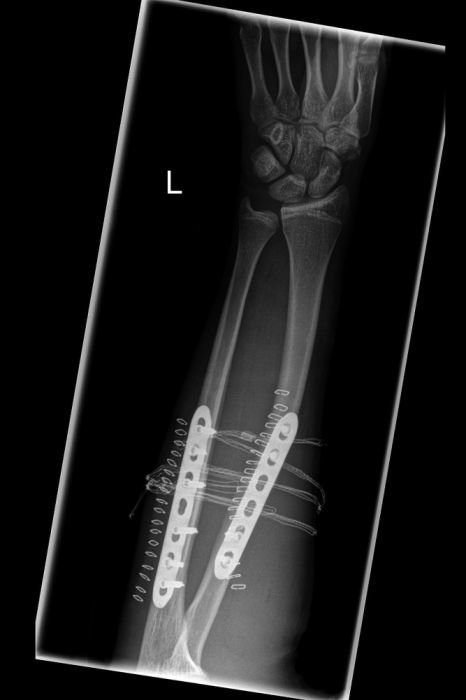

Pro Jenda : ačkoliv to tak vůbec nevypadá, byl to pád v téměř nulový rychlosti. Pěknej polet přes ródla rovnou na předloktí.

Pro capis : rád bych napsal " naštěstí to není moje ruka", ale jelikož je to levačka syna … Jinak je bez sádry a docela v pohodě.